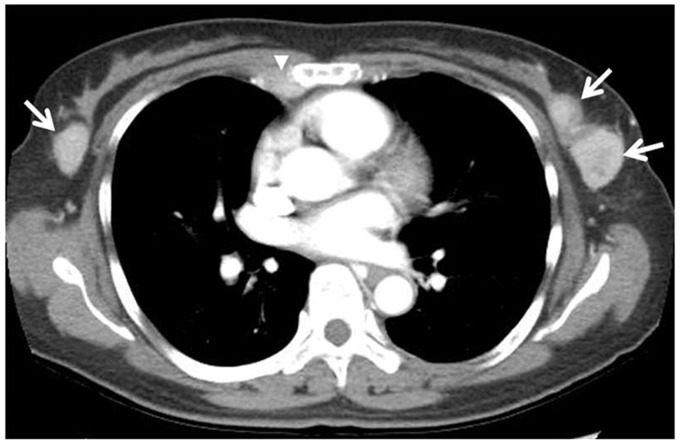

乳腺浆细胞瘤(BP)是一种极为罕见的多发性骨髓瘤(MM)的髓外表现。我们报告一例罕见病例的影像学发现,其中BP是MM的初始表现。一名53岁的女性,无相关病史,接受胸部计算机断层扫描以评估间歇性夜间前路胸痛,发现双侧多发乳房肿块。超声引导下的核心穿刺活检证实为BP。

Breast plasmacytoma (BP) is an extremely rare extramedullary manifestation of multiple myeloma (MM). We report the imaging findings of an unusual case in which BP was the initial presentation of MM. A 53-year-old woman with no contributory medical history underwent chest computed tomography to evaluate intermittent nocturnal anterior chest pain, and bilateral multiple breast masses were found. Following an ultrasound-guided core needle biopsy, these lesions were confirmed to be BP.